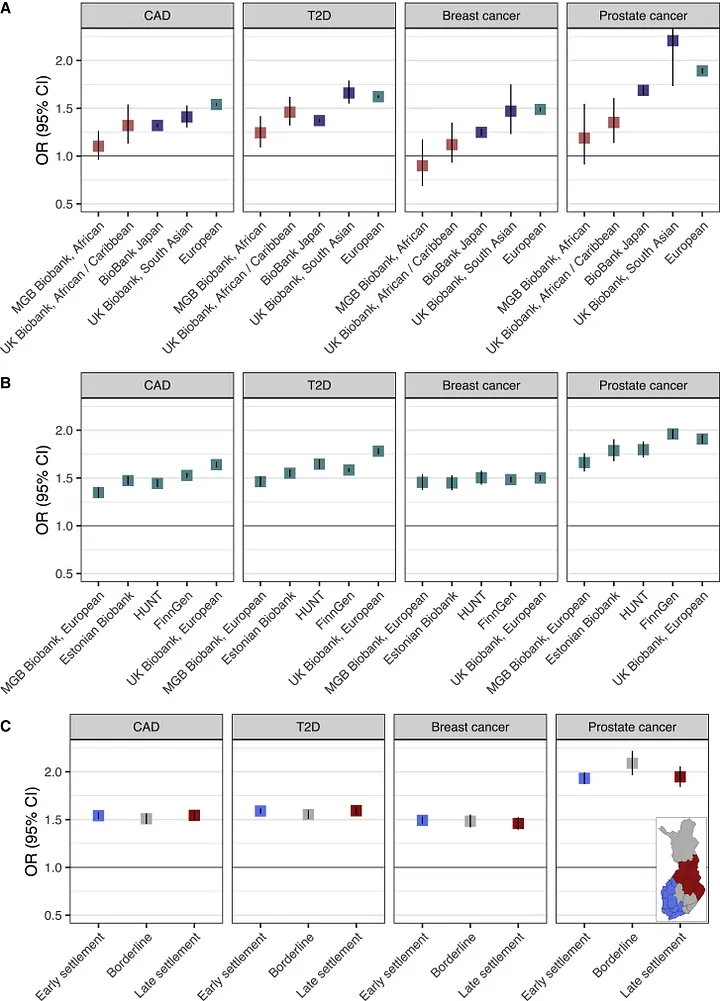

Allelica’s ancestry first approach for clinical PRS implementation

Polygenic Risk Scores (PRS) are a powerful tool in precision medicine, offering insights into an individual’s genetic predisposition to various diseases.

How to apply polygenic risk scores across diverse populations

Polygenic risk scores (PRS) predict the likelihood of developing complex diseases based on an individual’s genetic makeup. However, their application across different genetic ancestries presents numerous challenges.

Allelica White Paper: Multi Ancestry PRS for Coronary Artery Disease

Development and Validation of Multi-Ancestry Polygenic Risk Scores for Coronary Artery Disease